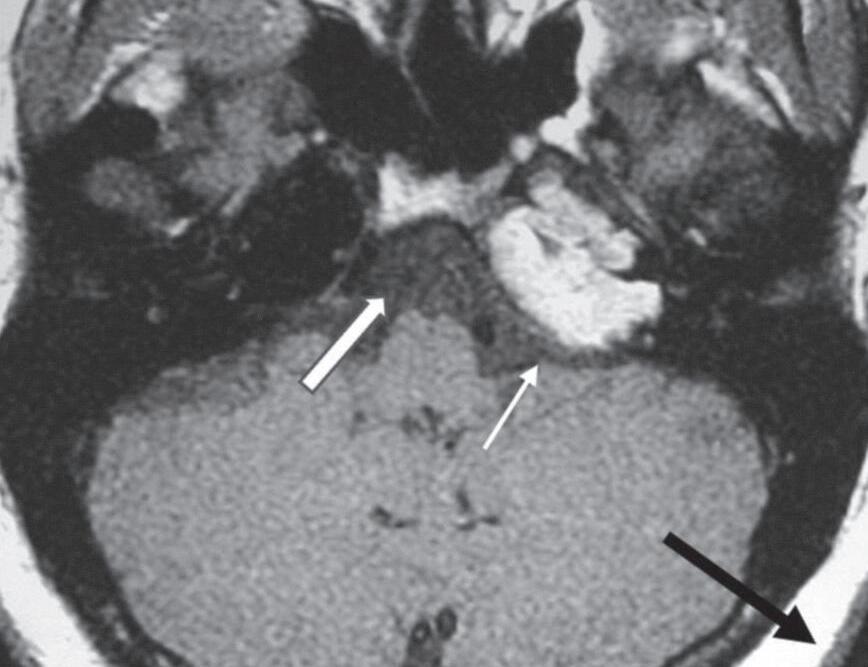

Fig. 1-16. Granuloma de colesterol no ápice petroso: RNM sequência axial T1 (a): lesão expansiva no ápice petroso, comprimindo a ponte, compatível com granuloma de colesterol, com sinal hiperintenso na sequência T1 (seta curta); liquor com sinal hipointenso (seta branca larga); gordura subcutânea com sinal hiperintenso na sequência T1 (seta preta longa). RNM sequência axial T1 com supressão de gordura; (b): a lesão persiste com sinal hiperintenso na sequência T1 com supressão de gordura (seta); liquor no quarto ventrículo com sinal hipointenso (seta larga); gordura subcutânea suprimida. RNM axial T1 com subtração das sequências pré e pós-gadolínio; (c): demonstra apenas áreas de impregnação pelo agente paramagnético, na periferia do granuloma de colesterol (seta). RNM axial T2; (d): lesão expansiva no ápice petroso com depósito periférico de hemossiderina, halo de sinal hipointenso (seta curta); liquor com sinal hiperintenso no quarto ventrículo (seta longa).